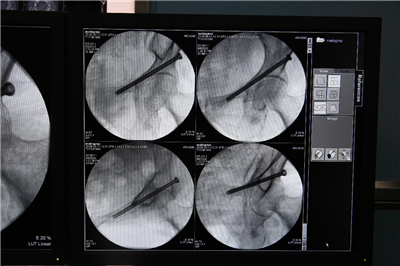

术后各个位置拍摄,验证空心钉完美入位: